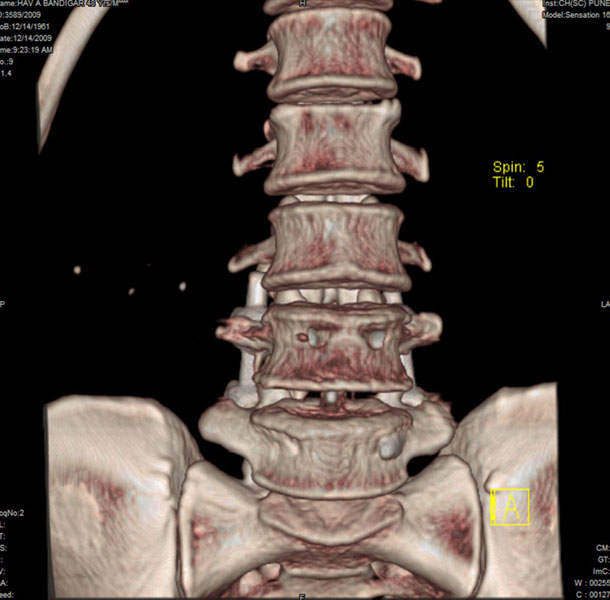

Spondylolisthesis malformations

Spondylolisthesis implies slippage of one lumbar vertebra over the next one, causing pain and nerve compression. Patient can also have difficulty in walking and numbness of the legs. Usually these patients need evaluation lumbar spine by MRI and CT scan, followed by spinal instrumentation and fusion.